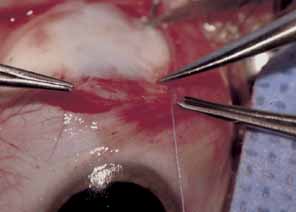

The muscle is then exposed; Tenon's capsule and the intramuscular septum are then dissected free (Figs. 1, 2, and 3). For a rectus muscle recession, a double-armed absorbable suture with a half circle needle is passed transversely through the muscle tendon, approximately 1 mm posterior to its insertion (Fig. 4 and 5). This suture is secured in place at both the superior and inferior poles of the muscle with locking bites. The muscle is disinserted from the globe.

Some surgeons prefer to combine bilateral medial rectus recession with resection of the lateral rectus muscle tendon. The lateral rectus muscle is isolated; Tenon's tissue and the intramuscular septum are dissected away for approximately 3 to 4 mm more than the desired resection. The amount of muscle tendon to be resected is measured from the insertion with a caliper. A double-armed absorbable suture is placed through the center of the muscle; it is passed transversely to the margin, where a locking bite is taken. A second suture is placed across the remaining muscle half and locked at the margin. A hemostat is then placed across the entire muscle, just anterior to the sutures. The muscle is disinserted from the globe, leaving a small stump. Muscle anterior to the hemostat is excised. The previously placed sutures are passed through the original insertion, each in a crossed swords fashion, so that the needle tips cross. The muscle is then pulled up and tied in place. Conjunctiva is pulled over the muscle and closed according to the surgeon's preference.